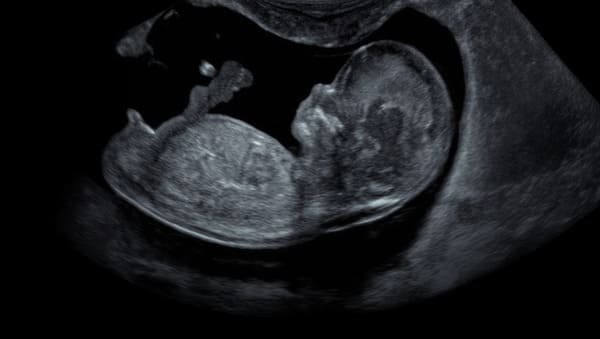

Vous avez examiné attentivement votre échographie du premier trimestre, remarqué que le tubercule génital pointait vers le haut, et selon la théorie du bourgeon, vous vous attendiez à un garçon. Or, quelques semaines plus tard, l’échographie morphologique a révélé une fille. Ce genre de revirement est beaucoup plus courant qu’on ne le croit. Comprendre la fréquence de ces erreurs permet de mieux appréhender les limites réelles de cette méthode de prédiction populaire, mais souvent mal interprétée.

L’échographie T1, programmée entre 11 et 14 SA, sert avant tout à vérifier la bonne implantation du fœtus, mesurer la longueur cranio-caudale, évaluer la clarté nucale (un marqueur de risque de trisomie 21) et dater la grossesse avec précision.

La lecture du sexe n’est pas son objectif principal. Elle peut avoir lieu, à la demande des parents, uniquement si le cliché s’y prête. L’interprétation du bourgeon est donc un bonus, et comme tout bonus, il faut savoir le relativiser.